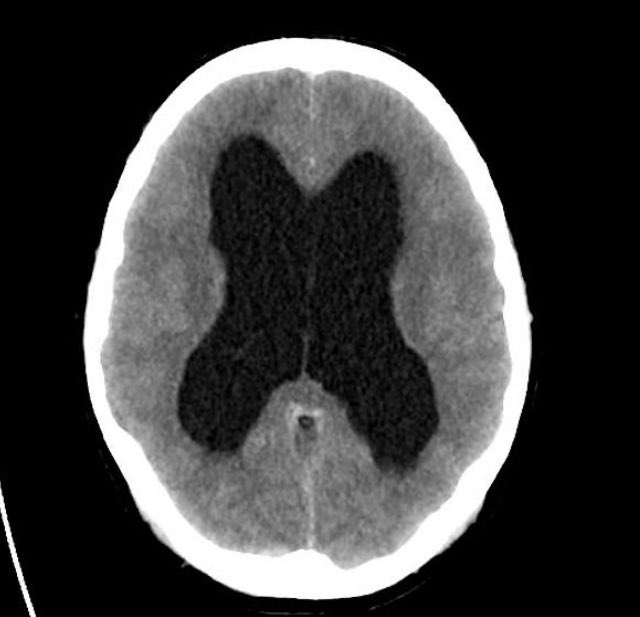

▫️Non-communicating Hydrocephalus

✳️ dilated lateral and third ventricle, but normal fourth ventricle.